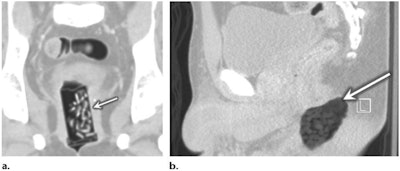

Body packing

Risks of body packing, or smuggling drugs by packing them inside the body, include packet rupture and ensuing drug absorption, localized ischemia, ulceration, and perforation.